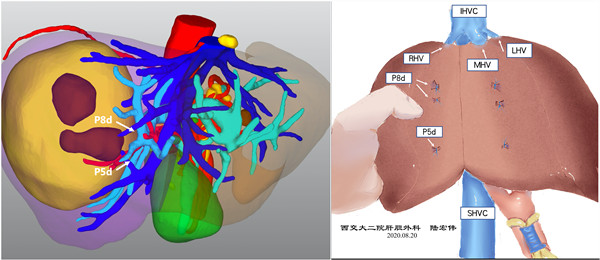

术前经过系统评估,患者存在肝硬化,肝功能属Child B级且ICGR15 20%,考虑到肿瘤的根治性,规则性肝切除是首选手术方案。术前三维重建提示若行右半肝切除,剩余肝体积仅占标准肝体积的36%,患者手术耐受性极差,术后肝功能衰竭风险极高。面对患者及家属无助的眼神,陆宏伟教授团队毅然接受了这次挑战。为了保证手术安全,决定先行保肝一周观察,在一周的保肝治疗后患者肝功能状况出现明显好转,评估达Child A级,但考虑到ICGR15仅为20%,按照右半肝切除其剩余肝体积应占标准肝体积的至少60%,术后肝衰风险仍然极高。陆宏伟教授团队展开详细术前小组讨论,在影像学评估的基础上,结合苏黎世大学和东京大学的肝切除限量标准,最终决定行解剖性的肝段切除,即Ⅵ、Ⅶ段和Ⅴd、Ⅷd亚段切除。术中在麻醉团队张晓琴教授、李伟教授和杨毅猛主治医师的保驾护航和手术室郭宁护师和刘儒忠护士的精密配合下,行经超声引导精准目标肝段切除。手术历时4小时,术中出血约300ml,术后未出现小肝综合征等肝功能不全表现,目前患者病情平稳,康复顺利,拟近期出院。

术前3D评估 手术示意图